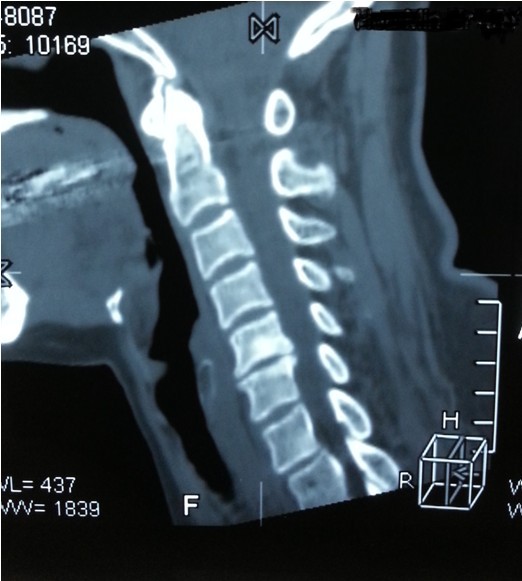

我院副院長兼脊柱科主任劉志安詢問病史后,詳細(xì)查體并攝片,發(fā)現(xiàn)患者是頸椎間盤突出,骨質(zhì)增生,壓迫頸椎神經(jīng),引起頸肩部酸脹難忍,雙手麻木乏力,若不盡快處理,癥狀將進(jìn)一步加重,建議患者盡早手術(shù)治療,否則將喪失最后的手術(shù)時機(jī),有致癱瘓的可能。

一開始,處于對手術(shù)以及住院費(fèi)用的恐懼,患者要求保守治療,可是如此嚴(yán)重的椎間盤突出,保守治療根本無法解除對頸椎的神經(jīng)的壓迫。劉副院長詳細(xì)向患者講述其病情起因,發(fā)展,變化,轉(zhuǎn)歸,并表示,患者頸椎手術(shù)總費(fèi)用預(yù)計(jì)在5萬以內(nèi),報(bào)銷后自費(fèi)約4萬左右,考慮患者家庭困難,可聯(lián)系紅十字基金會予以適當(dāng)?shù)难a(bǔ)貼,考慮再三,最終患者選擇到我院手術(shù)治療。手術(shù)結(jié)束后,患者慢慢開始恢復(fù),頸肩部酸脹不適癥狀消失,雙手麻木乏力癥狀較術(shù)前大為緩解,兩周后出院,患者及家屬對手術(shù)治療效果,醫(yī)生護(hù)士服務(wù)態(tài)度,以及花了3萬元就解決困擾多年的疾病均表示非常滿意。